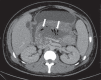

Acute pancreatitis is an inflammatory condition caused by intracellular activation and extravasation of inappropriate proteolytic enzymes determining destruction of pancreatic parenchyma and peripancreatic tissues. This is a fairly common clinical condition with two main presentations, namely, endematous pancreatitis - a less severe presentation -, and necrotizing pancreatitis - the most severe presentation that affects a significant part of patients. The radiological evaluation, particularly by computed tomography, plays a fundamental role in the definition of the management of severe cases, especially regarding the characterization of local complications with implications in the prognosis and in the definition of the therapeutic approach. New concepts include the subdivision of necrotizing pancreatitis into the following presentations: pancreatic parenchymal necrosis with concomitant peripancreatic tissue necrosis, and necrosis restricted to peripancreatic tissues. Moreover, there was a systematization of the terms acute peripancreatic fluid collection, pseudocyst, post-necrotic pancreatic/peripancreatic fluid collections and walled-off pancreatic necrosis. The knowledge about such terms is extremely relevant to standardize the terminology utilized by specialists involved in the diagnosis and treatment of these patients.